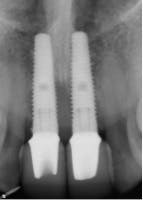

The oral surgeon, Dr. Richard Kim, D.D.S., M.D., explained how the procedure went. “When the patient first came in, she was put to sleep with intravenous general anesthesia. When she was asleep, I removed teeth numbers eight and nine. For immediate extraction with implant placement, the first initial pilot hole is placed a little bit lingually from the extraction site. You want the top of the implant to come out where the tooth cingulum would be so that more porcelain can be placed toward the buccal of the crown. After this, you go in with a 2-millimeter wide twist drill, then a larger tapered twist drill, and keep increasing the diameter of the drill until you reach the desired size, which was 4.3 mm in this case. I used Tapered Groovy Titanium Nobel Biocare implants for the patient at a size of 4.3 mm in diameter. The implants had threads which made it a little wider so it could engage the bone. I then used a torque wrench to tighten the implant into the bone and I was able to obtain a force of 45 Ncm2, which tells you the primary stability of the bone. I then placed bone allograft, which included BMP-2, to promote bone regeneration. The last step was securing the healing abutments, suturing up the tissue, and adjusting the flipper to fit.” (Refer to figure 4.)